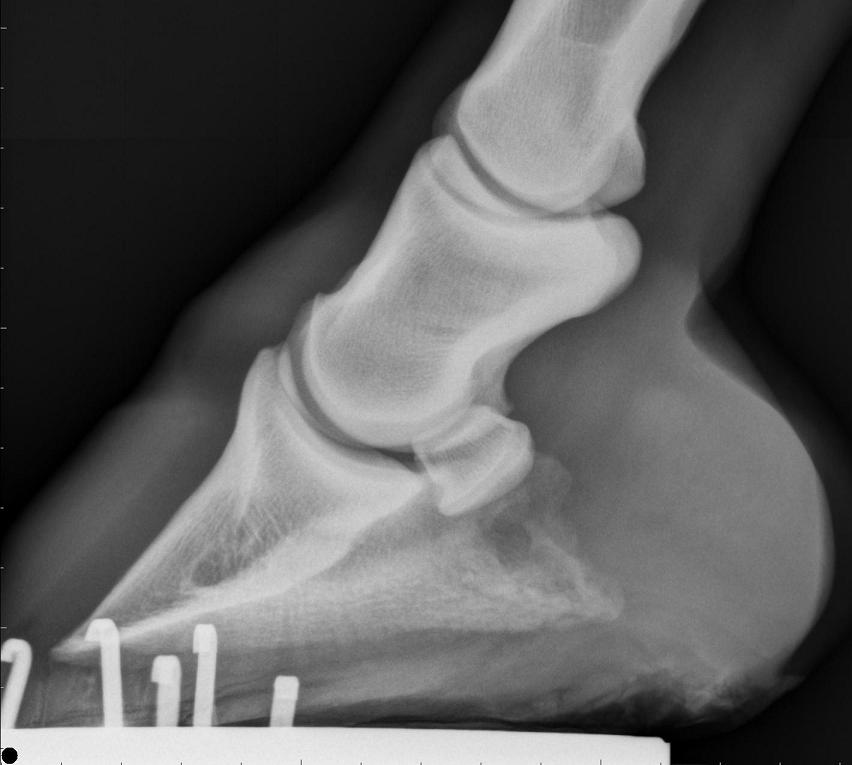

RF Lateral

right front lateral

1) I believe your veterinarian is saying poor foot balance has put extra stress on the coffin bone as demonstrated by the changes in the tip he describes. He believes that balancing the foot and relieving break over and reduced exercise the horse in time will come sound for full work again. I have to ask did he also do a posterior digital block prior to the ab. ses. block?

3) I cannot count how many horses with both diagnosed and undiagnosed lameness of the foot that were remarkably more sound with proper balancing, squaring off of the toe, and rockering the bottom of the foot or shoe. The LF lateral above suggests to me there is a fair about of horn out in front of the coffin bone to deal with. Maybe instead of you talking to the vet you need to put the vet in touch with the farrier.

Compared to the radiographs, it looks like he found a fair amount of toe to remove, good for him. Assuming as low as possible with as small a dose as possible principles were used, the improvement with the PDN then sound with AbSes is further support for tagging this at the tip of the toe or somewhere along a line between the tip and the coffin jt.